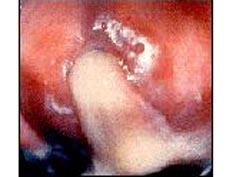

如图所示,急性宫颈炎患者的主要临床表现是 ( )A、痛经B、腹痛C、阴道分泌物增多D、月经淋漓不尽E、阴道接触性出血

问题 如图所示,急性宫颈炎患者的主要临床表现是 ( )

选项 A、痛经 B、腹痛 C、阴道分泌物增多 D、月经淋漓不尽 E、阴道接触性出血

答案 C